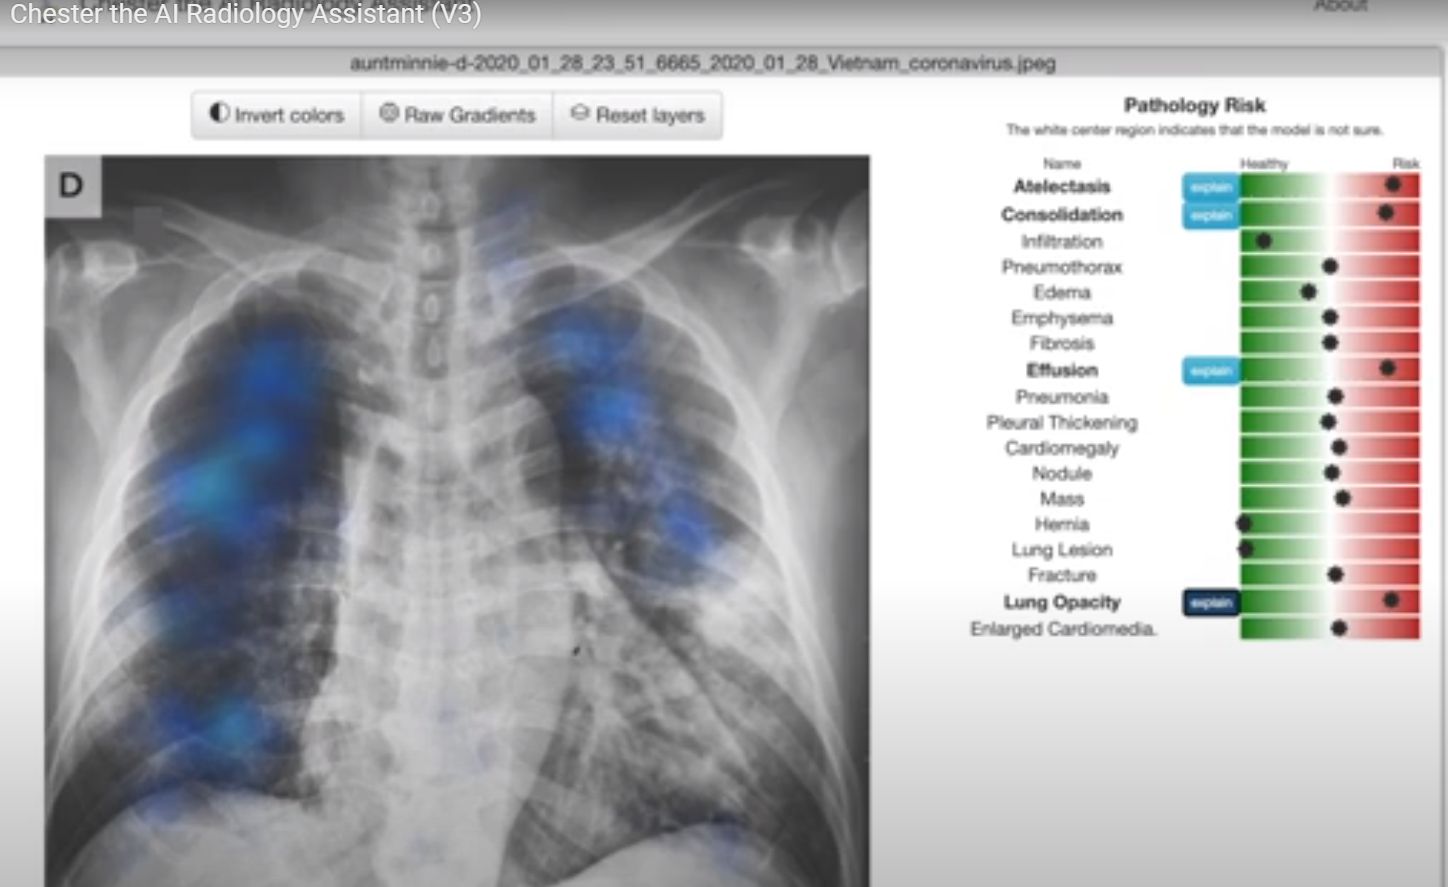

Chester, deşi este încă rudimentar, poate diagnostica atelectazia, cardiomegalia, pneumonia, pneumotoraxul, poate vedea noduli, edeme, emfizem, fibroză, îngroşarea pleurală şi hernii cu o precizie de 80%. O scală culisantă de la verde spre roşu indică probabilitatea de diagnostic pentru fiecare afecţiune, variind de la „sănătos” la „risc”, având posibilitatea să prezică 14 boli.

Tehnologia i-a permis lui Chester să analizeze scanările toracice cu un sistem bazat pe web, dar rulat local. Interfaţa instrumentului este concepută pentru a fi simplă şi cuprinde trei componente principale: detectarea în afara distribuţiei, predicţia bolii şi explicaţia predicţiei. După ce o persoană îşi încarcă radiografia, durează aproximativ 12 secunde pentru a încărca iniţial modelele, 1,3 secunde pentru a calcula graficele relevante şi încă 17 secunde pentru a calcula gradienţii pentru a explica predicţiile sale.